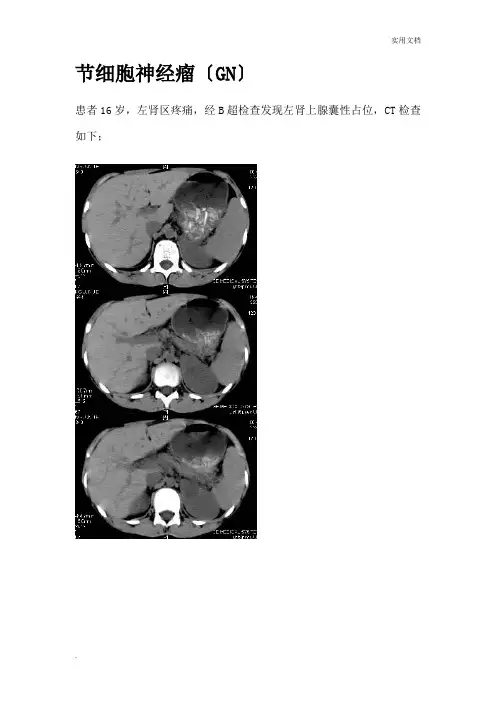

节细胞神经瘤〔GN〕患者16岁,左肾区疼痛,经B超检查发现左肾上腺囊性占位,CT检查如下;CT表现:左侧肾上腺区可见一较大囊性为主的占位性病变,其内可见少许实性成分,增强后实性成分可见明显强化,病灶边缘清晰,与周围结构分界清;肾上腺节细胞神经瘤节细胞神经瘤〔GN〕节细胞神经瘤(ganglioneuroma, GN)是一种很罕见的神经源性良性肿瘤,起源于原始神经嵴细胞。

肾上腺节细胞神经瘤的CT表现:节细胞神经瘤为良性肿瘤,在CT上其边缘通常是光滑锐利的,包膜完整,与周围组织分界清楚,可呈圆形,椭圆形,新月形或分叶状,质坚硬;密度值多为不均质低密度灶,稍低于肌肉组织;强化后密度轻度增高或者延迟强化,但仍低于肌肉组织。